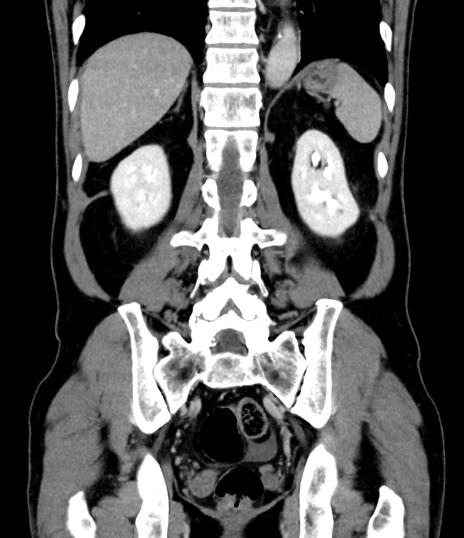

症例8(冠状断像)

【症例】 60歳代男性

【主訴】 黒色吐物

【現病歴】 4日前から嘔気自覚、2日前の朝食後にも嘔気あり、自分で手で嘔吐反射起こし嘔吐したところ血が混ざっていたため受診。

【既往歴】 5年前汎発性腹膜炎を伴う急性虫垂炎で手術、高血圧、前立腺肥大症、高脂血症

【身体所見】 腹部正中に手術癩痕あり 腹部平坦・軟圧痛なし膨満感あり

【データ】WBC 8400、CRP 4.54